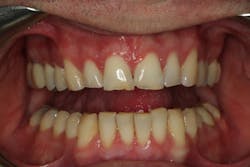

Darren had a lengthy dental history, but the chipping of his maxillary anterior teeth was his chief complaint. His main goal was to keep his teeth for as long as possible, and he was willing to do whatever it took to achieve that goal.

From the two-dimensional evaluation, the signs of occlusal instability were clear. Darren had very thin, chipping incisal edges, to the point where they were becoming transparent. The patient had almost worn shelves into the lingual of the maxillary anteriors, suggesting a restricted envelope of function. He also had wear into dentin in the anterior teeth as well as posterior teeth, and his anterior teeth had Class 1 mobility.

Esthetically, his maxillary incisal edges were slightly deficient vertically and needed to be lengthened, his length-to-width ratios needed to be improved, and his gingival contours were imbalanced. Darren had a slight cant with his occlusal plane, but he was not interested in correcting it. The mandibular incisal plane and arch form also required improvement. He was adamant that he wanted any esthetic changes to look natural and did not want “bright white” teeth.